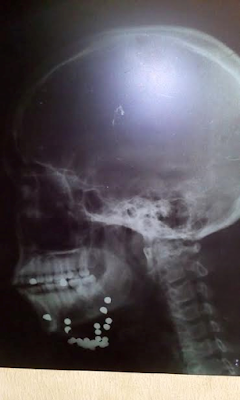

Photos: Nigerian man shot in the head by armed robbers regains consciousness after successful surgery

According to a Nigerian gospel singer, Hilary Madu, his brother Chijindu was shot in the head by armed robbers. The gunmen took his car and fled the scene leaving him to die.

He underwent a maxillofacial surgery on September 1. In an update posted on September 2, Mr Madu revealed that Chijindu has regained consciousness following a successful surgery. All glory to God! More before and after surgery photos after the cut.